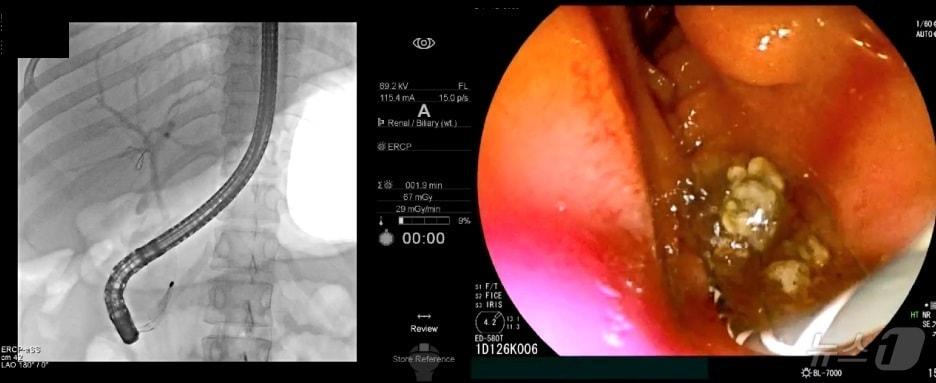

본문 이미지 - 내시경적 역행성 담췌관조영술(ERCP) 시술로 담관결석을 빼내는 모습./한림대 동탄성심병원 제

내시경적 역행성 담췌관조영술(ERCP) 시술로 담관결석을 빼내는 모습./한림대 동탄성심병원 제